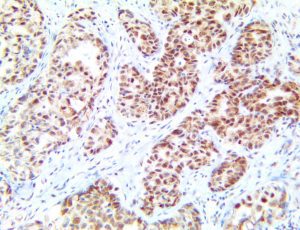

The first cytokines released are interleukin 1β (IL-1β) and tumor necrosis factor-α (TNF-α), which attract a variety of circulating white blood cells (WBCs) to the infection site, including neutrophils, monocytes, macrophages, and natural killer (NK) cells. This response, along with the antipathogenic chemicals released by these cells (i.e., complement), comprise the innate immune response. These cells directly attack the invading pathogen and also release additional cytokines, chief among them interleukin-1 and 6 (IL-6). IL-6 is essential for invoking the adaptive immune response, which calls T-cells, B-cells, and T helper (Th) cells to the infection site. IL-6 also stimulates further recruitment, proliferation and activation of macrophages.

It is the ICU physician who is most likely to witness one of the deadliest manifestations of the abnormal immunological response, the cytokine storm syndrome (CSS). This response is also referred to by some as the cytokine release syndrome (CRS). CSS is characterized by continuous activation and expansion of macrophage and lymphocyte populations, which secrete large amounts of cytokines, causing the cytokine storm. This massive cytokine release is akin to hemophagocytic lymphohistiocytosis (HLH) disease, a syndrome characterized by initial unchecked and persistent activation of cytotoxic T lymphocytes and NK cells.

This activation induces inflammatory monocytes to highly express IL-6, starting a localized and then systemic cascade effect that results in hyperproduction of IL-6, which accelerates the inflammatory process. Because IL-6 also increases vascular permeability, excessive levels cause blood vessels to become very leaky. This, along with clotting factors released from vascular endothelial cells, stimulates the coagulation cascade, resulting in microthrombosis (tiny clots), which leads to ischemia and tissue death of the kidney, intestines, heart, liver, brain and extremities.